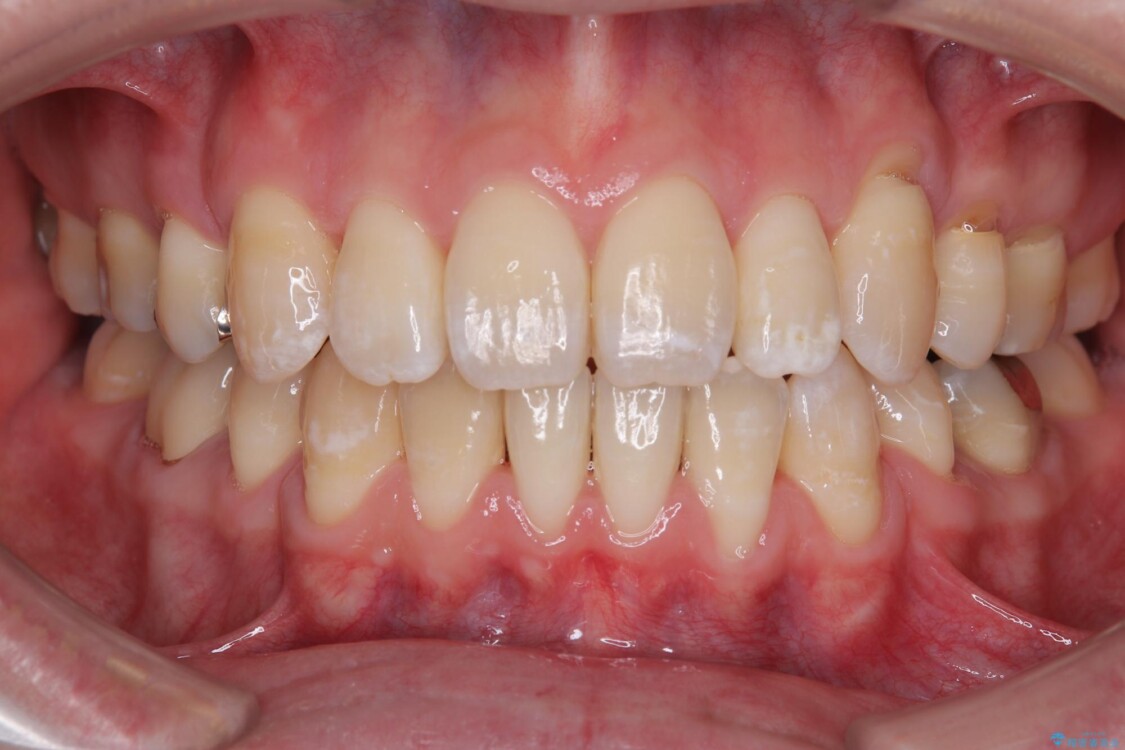

治療後

• 口元の突出感を改善!目立ちにくいワイヤー矯正で自信を持てる自然な横顔に 治療後画像

少しずつ前歯を後ろに下げていくことで、横顔のラインが整い、口元の“出っ張り感”が解消。

治療後には「自然に笑えるようになった」と嬉しいお声をいただきました。